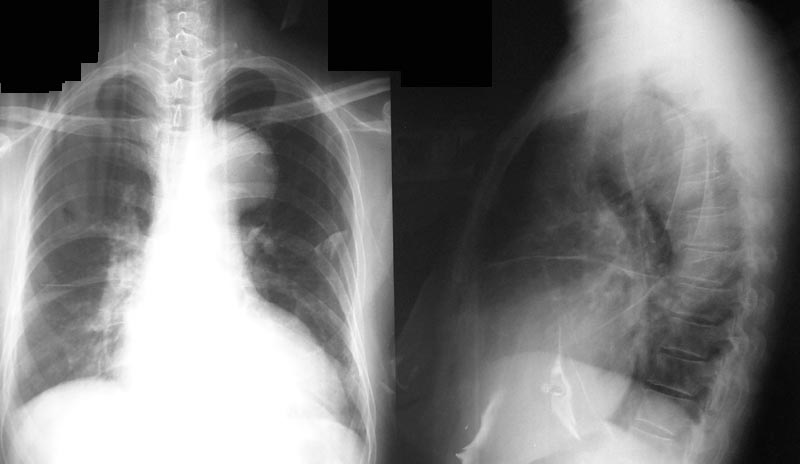

男,50y。

正位片左上纵隔旁可见突向肺野内半圆形密度增高影,边缘光滑,中心在纵隔内,与纵隔的夹角是钝角。侧位片可见升主动脉迂曲、扩张。

考虑:主动脉瘤,

正位片左上纵隔旁可见突向肺野内半圆形密度增高影,边缘光滑,中心在纵隔内,与纵隔的夹角是钝角与主动脉结关系密切。侧位片可见升主动脉局限性迂曲扩张。考虑主动脉瘤[emb18][emb7][emb6]